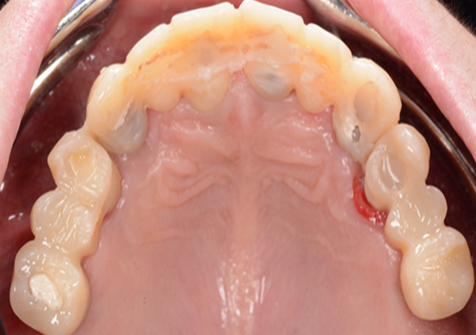

Clinical case: Extraction of all teeth in upper maxilla,

immediate implant placement, & provisionalization

- Courtesy of Dr. Iulian Filipov, Romania -

Keywords

AnyRidge, immediate placement, immediate provisionalization, maxillary fully edentulous case, initial stability, edentulous, Dr. Iulian Filipov, R2GATE, MEGA ISQ

Products:

AnyRidge implant system, Mega ISQ, R2GATE

“AnyRidge ensures long-term biological stability

& functionality even in

full-mouth rehabilitation case. ”